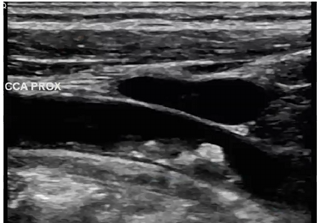

Patient presents to ultrasound department for preoperative work-up. Patient scheduled to have coronary artery bypass graft (CABG) in two days. Patient has HX of peripheral vascular disease, smoking, HTN and hyperlipidemia. You obtain this image. Consider following questions.

1. Is it possible to have plaque producing stenosis without symptoms?

2. What are the risk factors for atherosclerosis in this patient presentation?

3. Is this image diagnostic for hemodynamically significant stenosis? Why or why not.

Yes

Hx of peripheral vascular disease, smoking, HTN, hyperlipidemia. (Also has CAD because they are here for pre op for CABG)

No because power doppler only shows presence of flow and no velocity information